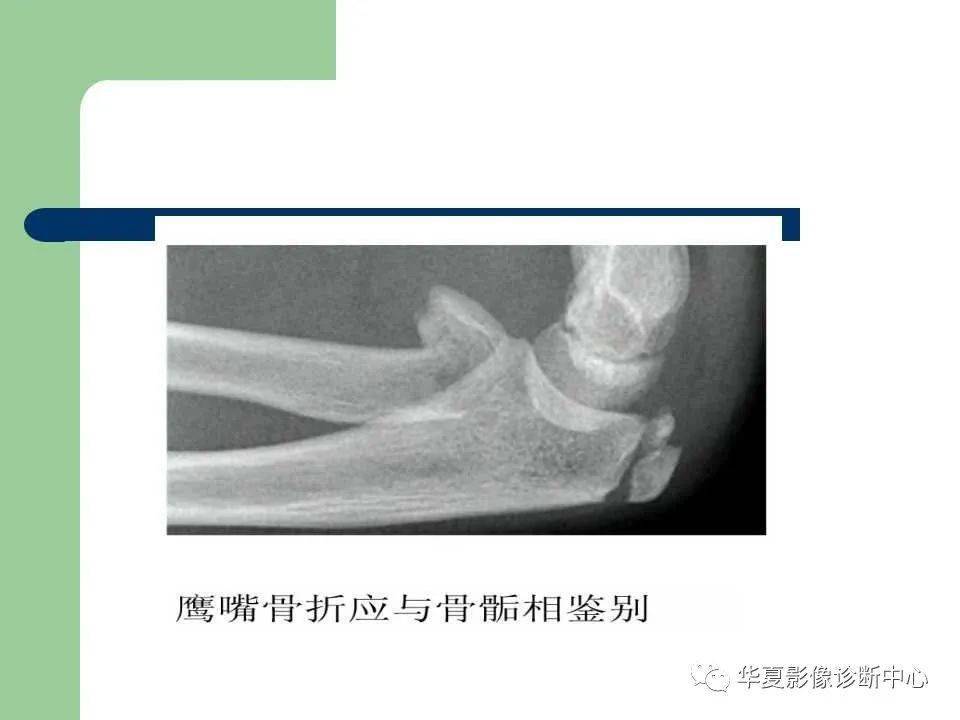

影像基础儿童肘关节损伤x线诊断

儿童肘关节外伤x线诊断